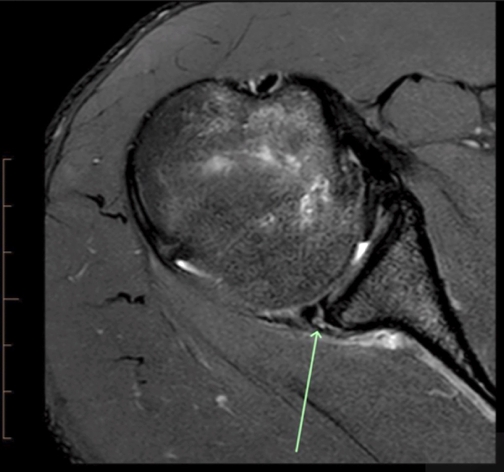

Athletes who experience a posterior shoulder dislocation may present with detachment of the posterior labrum from the glenoid rim (a ‘reverse Bankart lesion’ – see Figure 1). When the labral detachment is associated with a piece of the glenoid rim being avulsed, this is referred to as a ‘reverse bony Bankart lesion’(1).